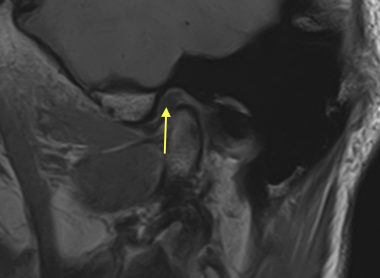

しかしMRI撮影で軟骨(黄色い矢印)がずれているのを確認していますので、やはり咬み合わせの長期安定を得るのは難しいと思われます。

最終のクラウンをセットし咬み合わせのチェックをデジタル機器で行ったところ、患者さんが自覚できない当たりが左奧に見つかりました。黄色の矢印I-26です。

この赤マークが付いているという事はインプラントに負荷が掛かっているという証拠です。